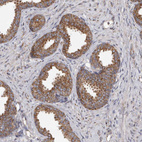

Immunohistochemistry analysis in human epididymis and skeletal muscle tissues using HPA027883 antibody. Corresponding CDK5RAP3 RNA-seq data are presented for the same tissues.